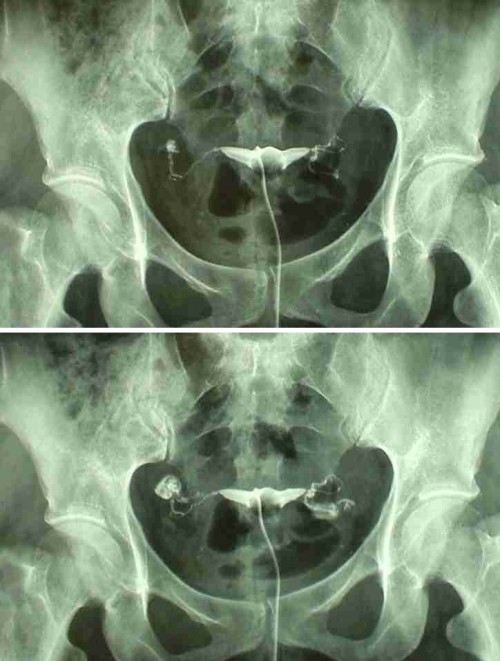

Медицинские снимки: Проходимость маточных труб

Раздел: Кадры-подсказки